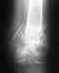

Здравствуйте дорогие травматологи-ортопеды!Помогите определиться с дальнейшим лечением.Внутрисуставной перелом локтевого сустава 8.07.2019операция 15.07.в сентябре рекомендовали снять гипс и разрабатывать локоть. в результате всё развалилось